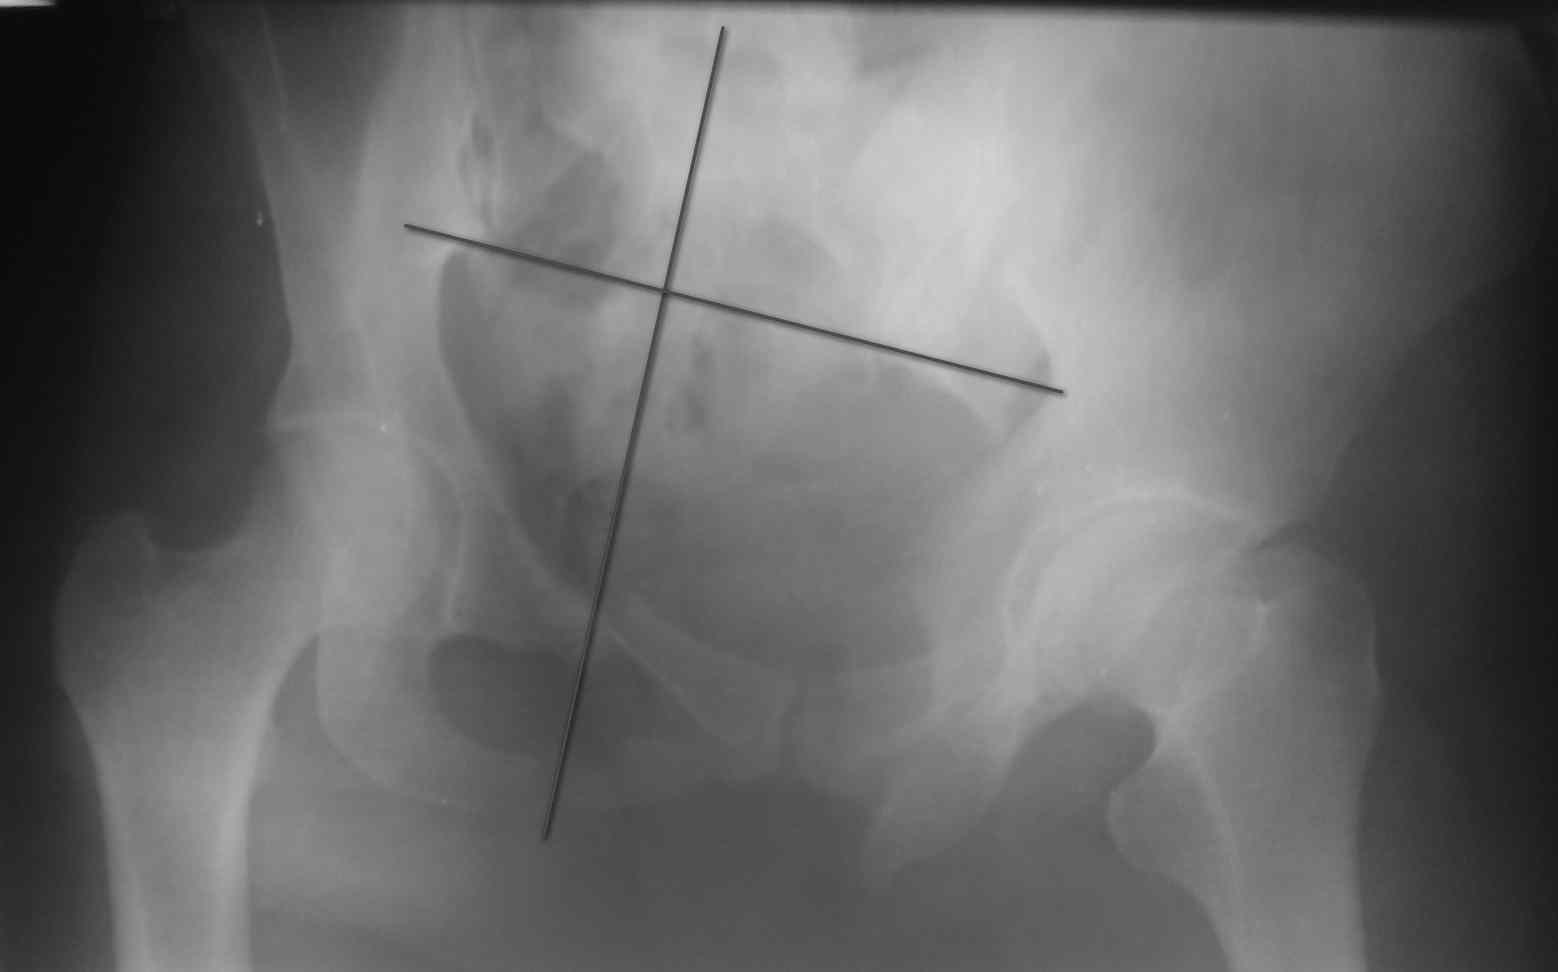

[Ortho] тяжелый таз

снимки